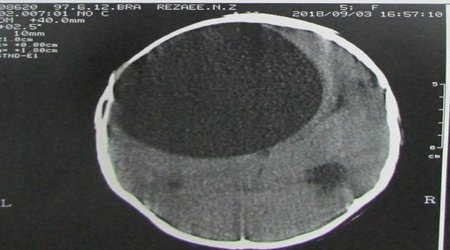

به گزارش مجید حیاتی روابط عمومی معاونت درمان، در یک عمل بی سابقه کیست هیداتیک با حجمی بالغ بر ۴۰۰ سی سی و قطری بیش از ده سانتی متر در سر بیمار، توسط جراح مغز واعصاب و ستون فقرات شاغل در بیمارستان آموزشی درمانی نهم دی،خارج گردید.گفتنی است این بیمار که یک پسر پنچ ساله می باشد بدنبال داشتن مشکلاتی از قبیل سردرد و تهوع و با تشخیص اولیه توسط متخصص اطفال و انجام سی تی اسکن و نیاز به جراحی، طی عمل چند ساعته این توده برداشته شد و در حال حاضر بیمار بدون هیچ گونه نقص عصبی بستری می باشد.